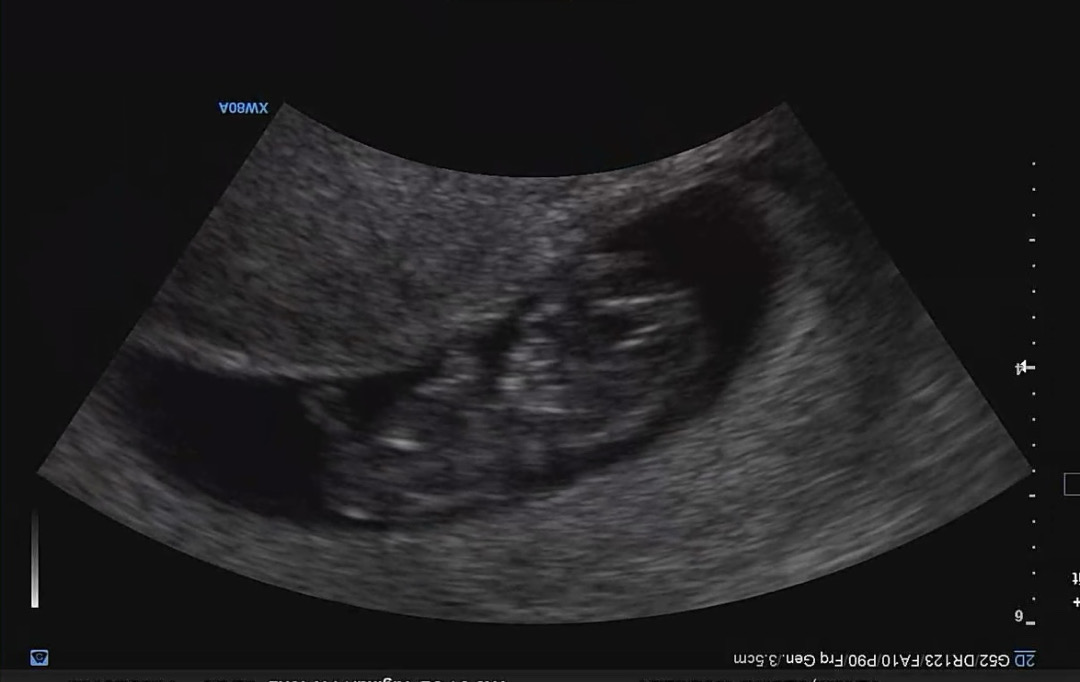

8주2일에 젤리곰 비스무리하게 보고 9주 6일 오늘 방문했더니 이제 꽤 누워 있는 아기(?) 모습처럼 보이는 것 같기두 하고..🥹 (제눈에만😂) 10주가 다가오니 갑자기 아랫배가 엄청 코오오옥, 코오오옥 찌르듯 아프고 우리우리 한 것 같아요ㅠㅠ 다른 분들은 입덧, 배 통증 좀 어떠신가요? 우리 모두 오늘은 보다 더 편안한 하루길 바래요🙏🏻

잘 자라고있는거같아용! 조금만 더 밝게 보여졌으면 좋앗을텐데 ㅜㅜ 아쉽네요~ 전 8주인데, 담당쌤이 점점 주수올라가면서 배 당기구 Y존 찌르르 하거나 칼로 콕콕 쑤실거라고 하셧눈데 이거는 아기랑같이 자궁이 커져서 그러는거니까 걱정안해도된다고 그러셧어요! 🥹